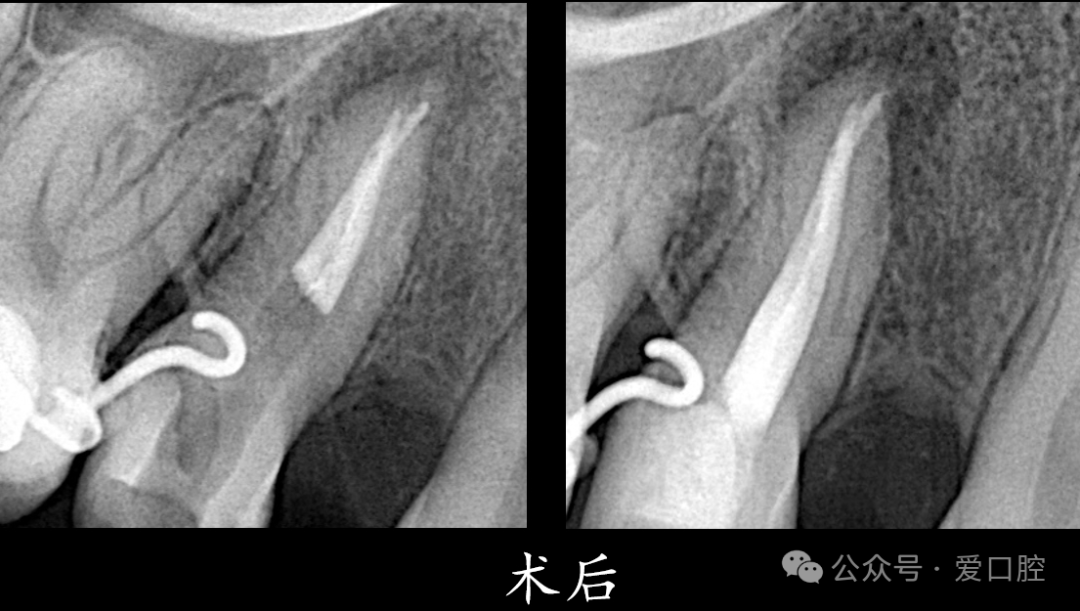

处置:15安放橡皮障后,去暂封,疏通,3%次氯酸钠溶液冲洗,Eddy荡洗(20秒3次), 蒸馏水冲洗,17%EDTA溶液冲洗,蒸馏水置换,吸干,AHplus糊剂+牙胶尖,热牙胶垂直加压法充填,流体封闭根管口,冠方树脂充填,调合,抛光。

医嘱:勿咬硬物,定期复查。